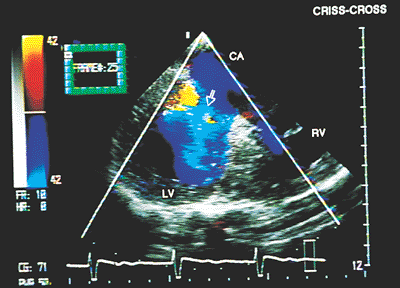

Crossed Atrioventricular Connection

Crossed A–V connection is not a specific type of connection; it corresponds, rather, to an alteration in the spatial relation between the atria and ventricles. The atrium situated on the right is connected to a ventricle located on the left; the left-sided atrium is connected to a ventricle positioned on the right. The A–V connection may be concordant or discordant. It is not easy to establish the diagnosis with transesophageal echocardiography in the transverse plane using monoplanar transducers, because the normal parallel relationship of the inlet chambers of the two ventricles is lost; in general, the abnormal spatial orientation of the A–V valves makes it difficult to observe both in the same sector.

Color Doppler can be useful in demonstrating that the ventricular filling flows cross each other (Figs. 8.2.38 and 8.2.39). Transesophageal and transgastric images in the longitudinal plane are of greater utility for aligning along the long axes of both ventricular filling flows.

FIGURE 8.2.38. Crossed atrioventricular connection. Two-dimensional and color Doppler study in a patient with criss-cross heart. The right portion of the common atrium (arrow) is connected to the anatomically right ventricle (RV) located on the left. CA, coronary artery; LV, left ventricle.

FIGURE 8.2.39. Crossed atrioventricular connection. When a crossed atrioventricular connection exists, the left portion of the common atrium (CA) connects (arrow) to the anatomically left ventricle (LV) located on the right. RV, right ventricle.